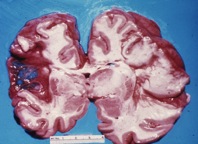

Late liquefactive necrosis

following an ischemic stroke

Brain tissue is very sensitive to insufficient oxygen and glucose supply, and is more susceptible to injury caused by ischemic bouts than most other tissue types. After three hours of ischemia permanent brain tissue damage occurs, and the affected area of the brain starts to undergo liquefactive necrosis.